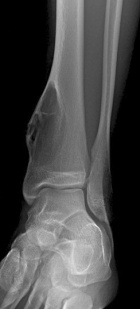

T.K. - 18 year old male with asymptomatic left ankle swelling for several months

Zoom image: Radiological image Radiological image.